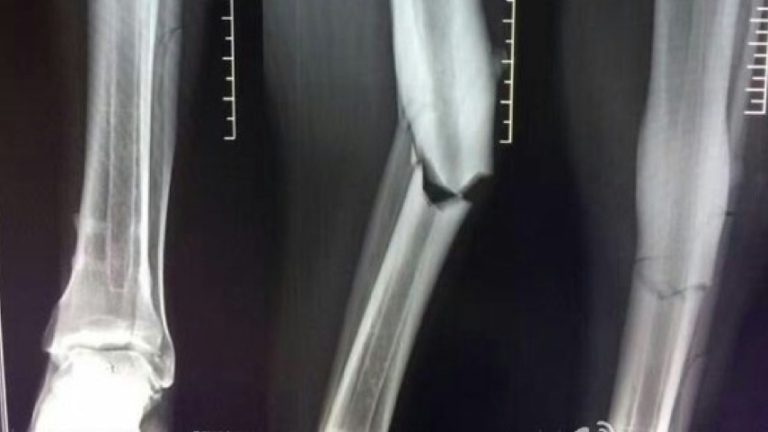

Звездата на Шанхай Шенхуа - Демба Ба получи ужасяваща контузия по време на мач от местното първенство в неделя. Днес бившият играч на Челси получи резултатите от скенера, от които стана ясно, че ще се завърне на терена чак след 8 месеца.